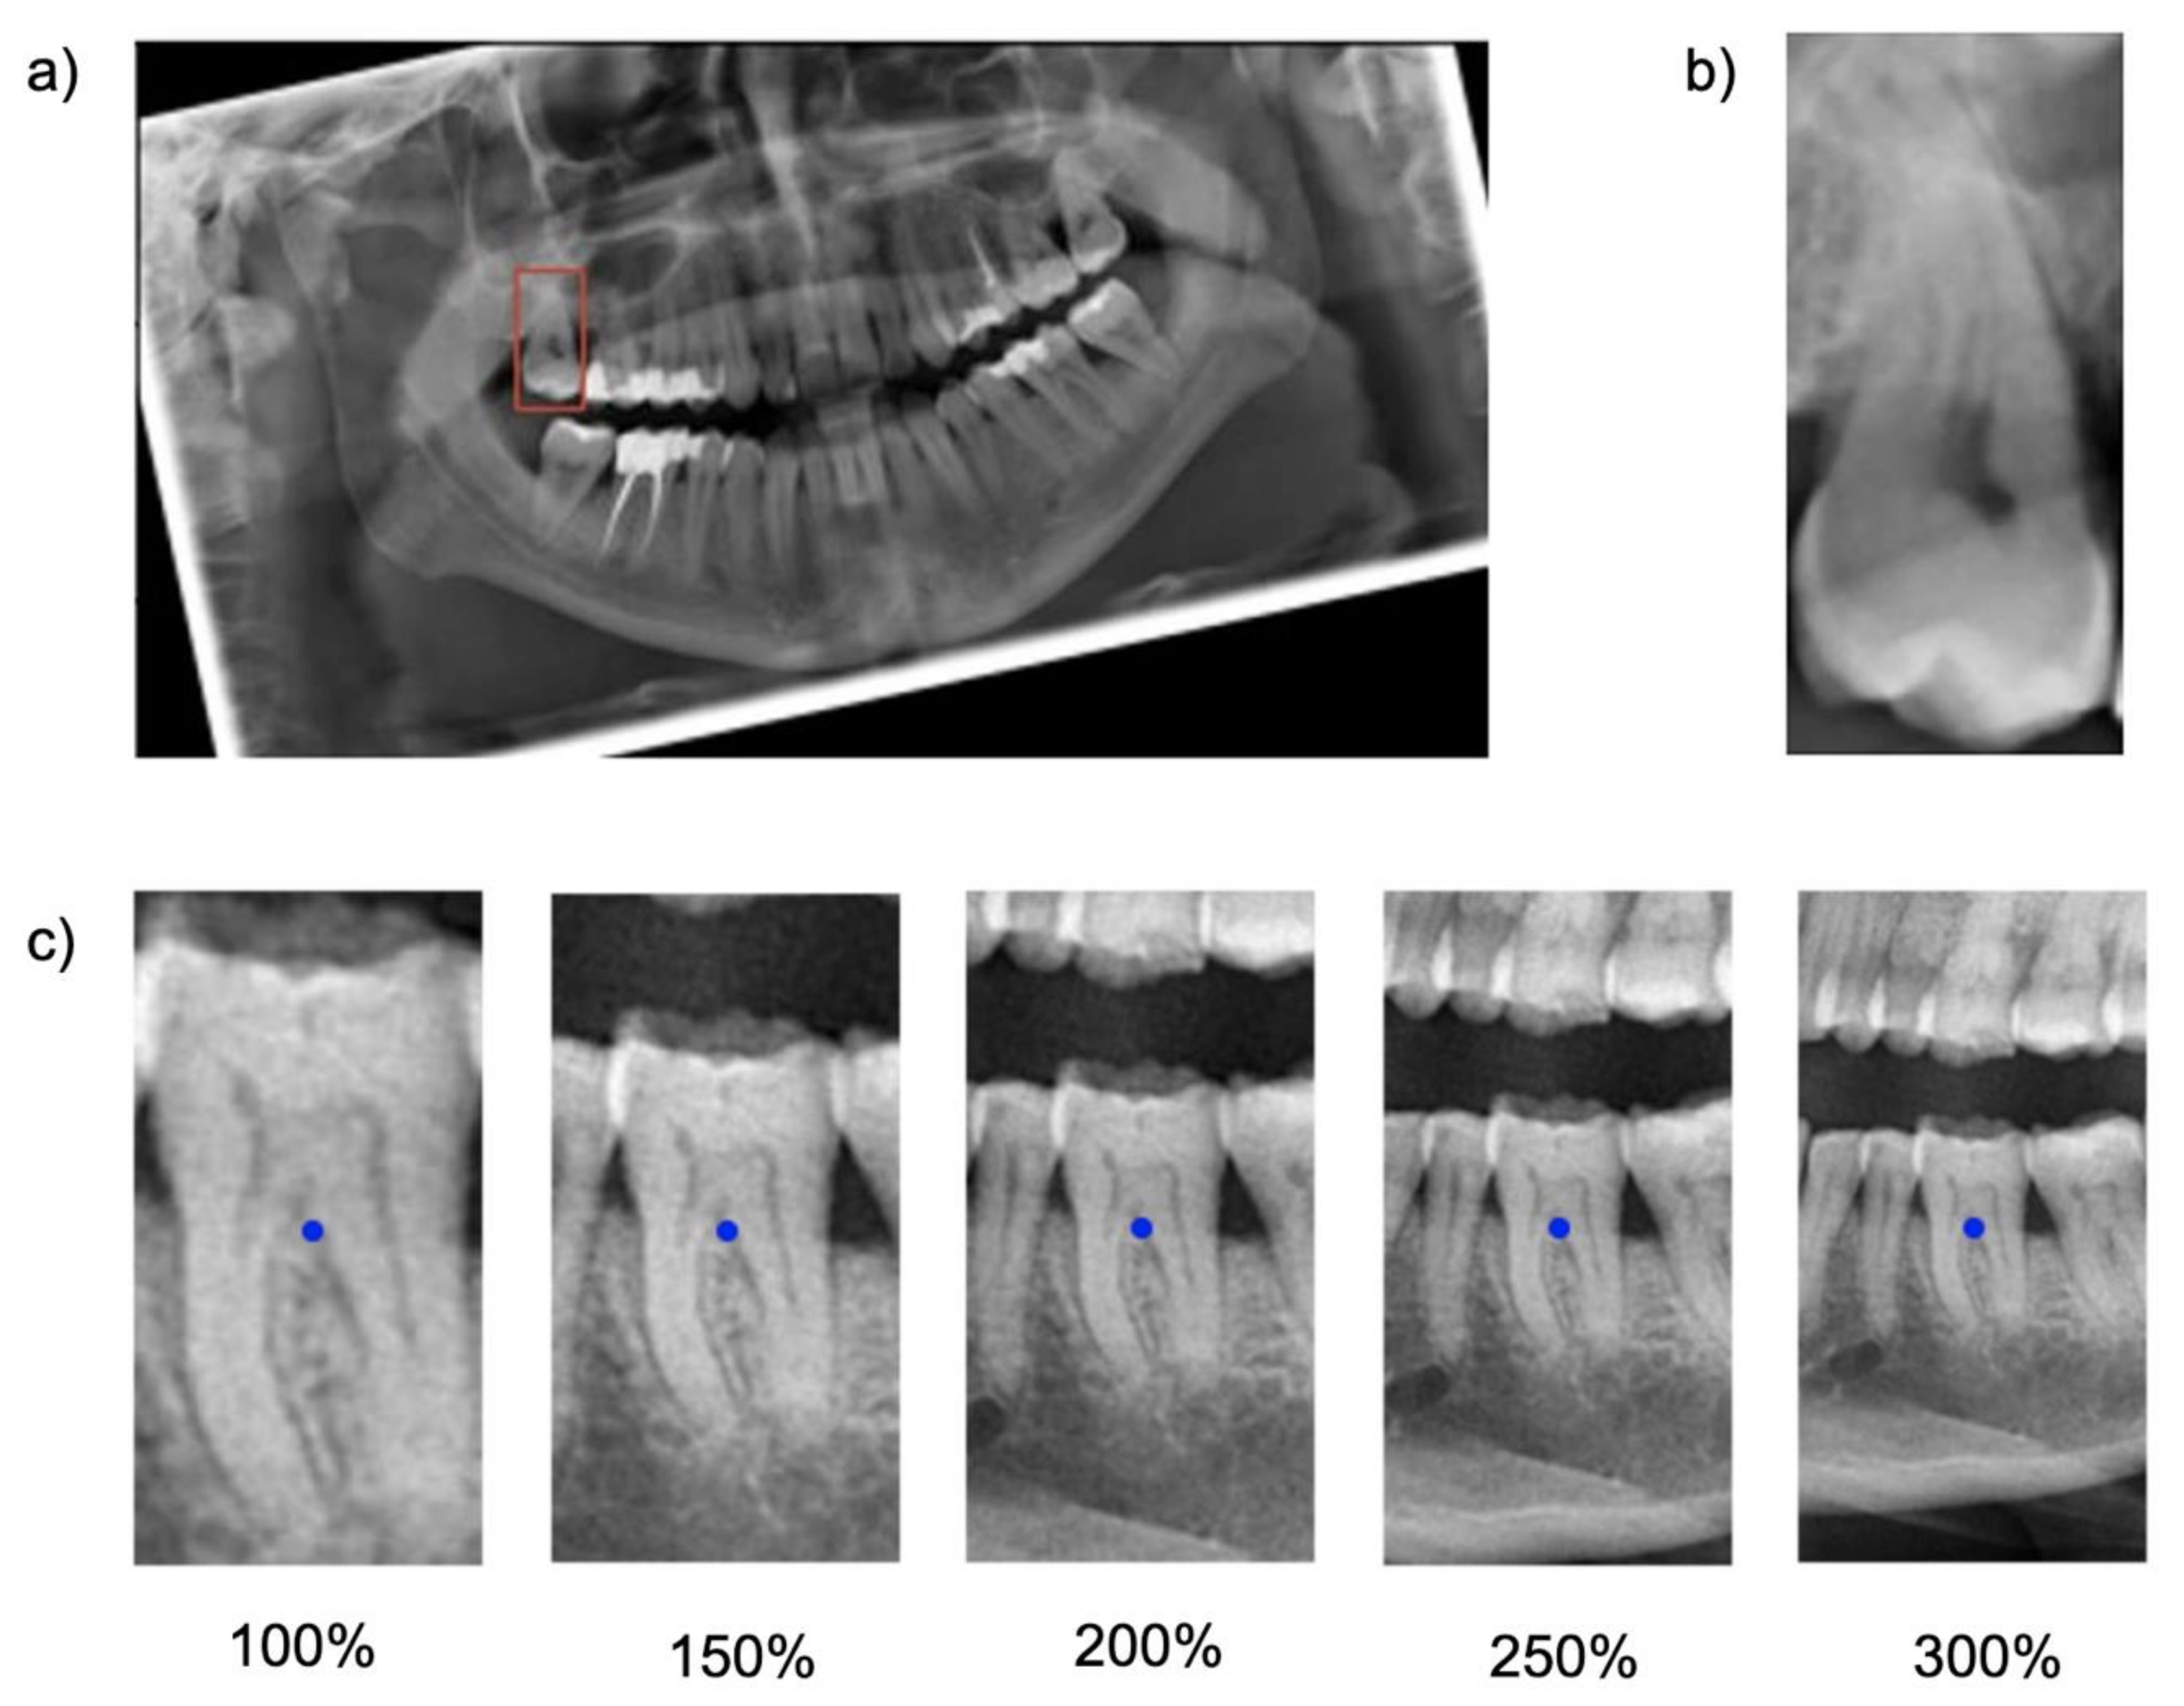

Cropping was repeated five times, each time with varying regional context information: The baseline bounding box size (100%) was scaled up to capture 150%, 200%, 250% and 300% of the baseline bounding box. The original aspect ratio was kept constant (see

Figure 1). Note that the tooth considered for the classification task was consistently located within the center of each image segment.

Figure 1).